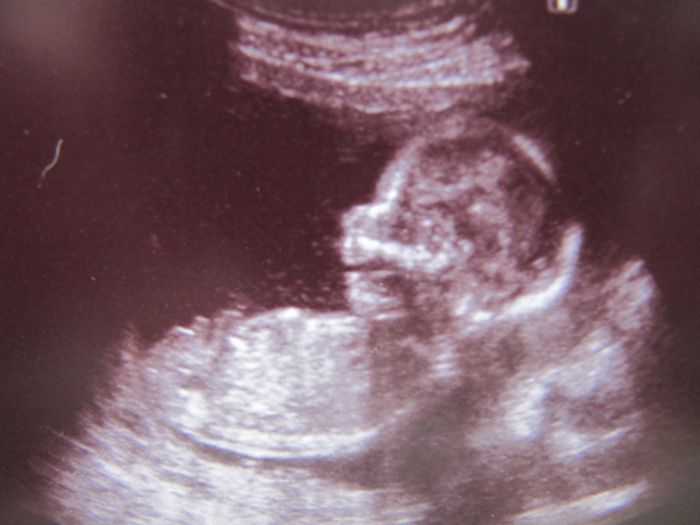

Tak se hlásím po dnešní genetice, zdá se být všechno v naprostém pořádku, tak jsem šťastná jak blecha, teď ještě v tom 20tt., ale věřím, že když dopadlo tohle dobře, tak i ten velký bude v pořádku. Je to definitivní kluk, pan profesor mi udělal i 3 fotky, jako dáreček (bez placení, na pohlaví jsem se neptala-sám se nabídnul, zda to chci vědět). Tak je připojuju, na jedné je z profilu s otevřenou pusinkou, na jedné zepředu-pěkně viditelná čočka v jednom oku a na poslední výbavička našeho frajera.

marse gratuluju a krasne fotecky, kukadla jako zrcadla